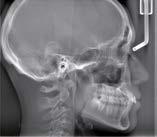

Partielle cephalometrische Aufnahmen

Die Bereiche, die für die Untersuchung nicht relevant sind, werden durch Ausblendung nicht bestrahlt. Es gibt drei partielle Aufnahmemodi für Ausblendungen, die die Röntgendosis reduzieren.